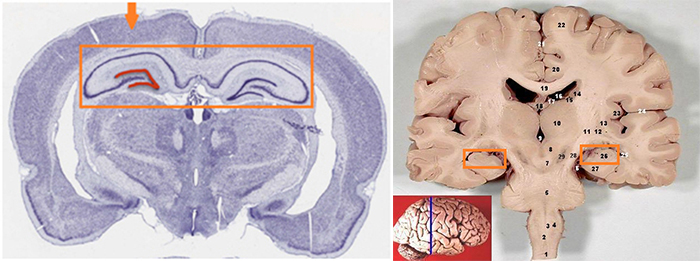

연구팀은 면역조직화학기법(immunohistochemistry)과 유전자표지 기술 등을 이용하여 신경전구세포 및 성숙한 신경세포의 표지 단백질을 정밀 분석했다. 그 결과, 해마의 치아이랑(dentate gyrus) 부위에서 신경전구세포가 존재하고 있으며, 일부는 새로운 신경세포로 분화하고 있었다.